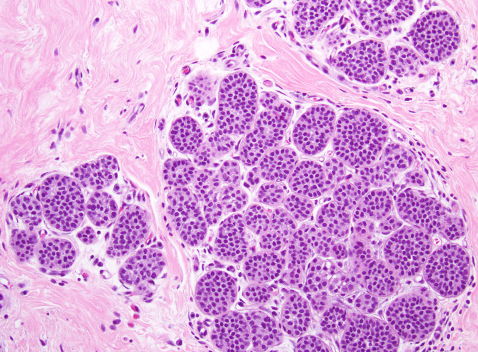

제자리암은 영어로 Carcinoma in situ라고 하며, 말 그대로 ‘제자리에 있는 암’을 의미합니다. 암세포가 생기긴 했지만, 기저막을 뚫지 않아 주변 조직으로 퍼지지 않은 상태를 말합니다. 이 단계에서는 세포가 비정상적으로 변했지만, 혈관이나 림프를 통해 다른 부위로 전이되지는 않습니다.

제자리암과 침윤암의 가장 큰 차이는 ‘퍼짐의 유무’입니다. 제자리암은 세포가 변형되었으나, 그 변화가 한정된 부위에 머무는 상태입니다. 반면 침윤암은 세포가 기저막을 넘어 주변 조직, 림프, 혈관 등으로 퍼진 상태를 말합니다. 따라서 침윤암은 수술, 항암, 방사선 치료 등 적극적 치료가 필요하지만, 제자리암은 비교적 관리 중심으로 접근할 수 있습니다.

제자리암은 건강검진이나 정기 세포검사에서 우연히 발견되는 경우가 많습니다. 대부분 증상이 없기 때문입니다. 예를 들어 자궁경부 제자리암은 자궁경부 세포검사(Pap smear)에서 비정상 세포로 확인되고, 조직검사로 확진됩니다. 유방 제자리암 역시 유방촬영이나 초음파에서 미세석회화 병변으로 나타나 진단됩니다.